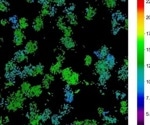

• Human RPE cells were transduced with an AAV vector containing a GPF reporter gene and an AAV5 capsid. Live imaging evaluated transgene expression up to 27 days after transduction.

• Quantification of the percentage of GFP-positive cells.

• Percentage of the area with GFP-positive cells over 28 days post-transduction increased over time and in a dose-dependent manner